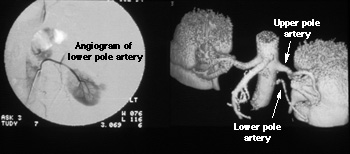

These two images show a patient with two renal arteries of the left kidney. The image on the left is an angiogram obtained by injecting contrast directly into the artery of the lower pole of the kidney. The image on the right is the corresponding 3-D CAT scan illustrating both the upper and lower pole arteries.